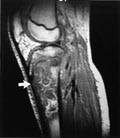

Utredning av medfødte hjertefeil med MR har tidligere vært omtalt i Tidsskriftet (8). Hovedindikasjonene for å undersøke pasienter med medfødte hjertefeil med MR er morfologisk fremstilling av hjertet og de store kar. Eksempler er måling av størrelse av sentrale lungekar ved Fallots tetrade, kontroll av koarktasjonsopererte med tanke på rekoarktasjon eller aneurismeutvikling og kontroll etter shuntoperasjoner. Måling av ejeksjonsfraksjon og karakterisering av ventrikkel- og klaffefunksjon ved kardiomyopatier og etter korreksjon av transposisjon av de store kar med Mustard- og Senning-teknikker er et annet eksempel. Klaffeinsuffisiens kan vurderes uten forstyrrende påvirkning av kateter som er ført gjennom klaffeapparatet, og uten rytmeforstyrrelser, som forekommer i forbindelse med kontrastmiddelinjeksjon. En fremstilling av sjeldne kardiale tumorer (fig 2) kombinert med MR-opptak gjennom både systole og diastole i samme snittplan og avspilt i sløyfe (cine-MR) for å vurdere eventuell klaffeaffeksjon og innvekst i myokard kan være av verdi preoperativt.

MR av hjertet har i løpet av 1990-årene utviklet seg fra å være et hjelpemiddel for anatomisk kartlegging av så vel store kar som intrakardial anatomi til å bli et sofistikert verktøy som kan måle en rekke fysiologiske parametere (9, 10). Global og regional myokardkontraktilitet i ventriklene kan måles, og tallrike artikler har beskrevet hvordan MR med sin tredimensjonale kvalitet kan brukes til nøyaktige volumbestemmelser av hele hjertet, de enkelte ventrikler og forholdet mellom ventriklene pre- og postoperativt. Nyere sekvenser har åpnet for nøyaktig kvantifisering av blodstrømmen i de store kar, beregning av shuntvolumer, utregning av gradienter over stenotiske kar eller klaffer, for å nevne noen muligheter.

Etter initial kartlegging og operativ behandling kan videre kontroll i de aller fleste tilfeller skje ved hjelp av en kombinasjon av MR og ekkokardiografi. Bare unntaksvis, som for eksempel ved vurdering av Fontan-operasjon, vil kateterisering være nødvendig. MR-angiografi på barn kan med fordel brukes til fremstilling av store kar intratorakalt (anomalier), store abdominalkar eller bekkenkar ved mistanke om okklusjon etter kateterisering. Oppløseligheten ved MR er fortsatt noe dårligere enn ved CT og angiografi, og andre begrensende faktorer er behov for sedasjon, manglende evne til samarbeid samt tilgjengelighet av undersøkelsen.